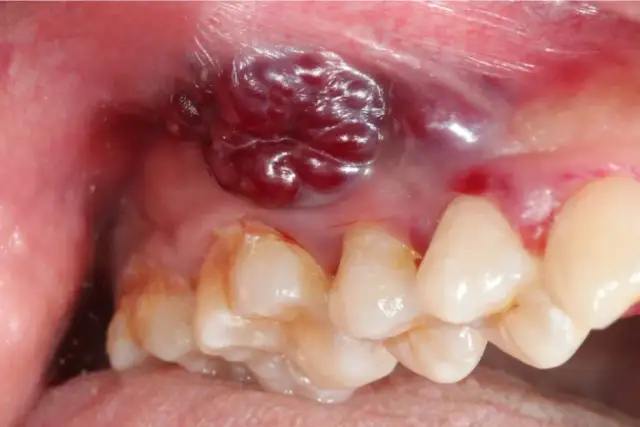

Rak dziąseł: jak wygląda i co robić, by uratować życie?

Jak wygląda rak dziąseł? Rozpoznaj wczesne objawy, czynniki ryzyka i kroki diagnostyczne. Sprawdź, jak wczesne wykrycie ratuje życie.